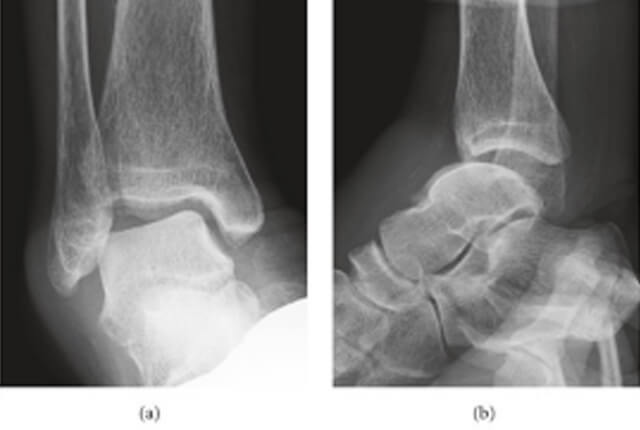

• ストレスX線撮影(前方引き出し・内反ストレス)で不安定性を確認します

ストレスX線撮影